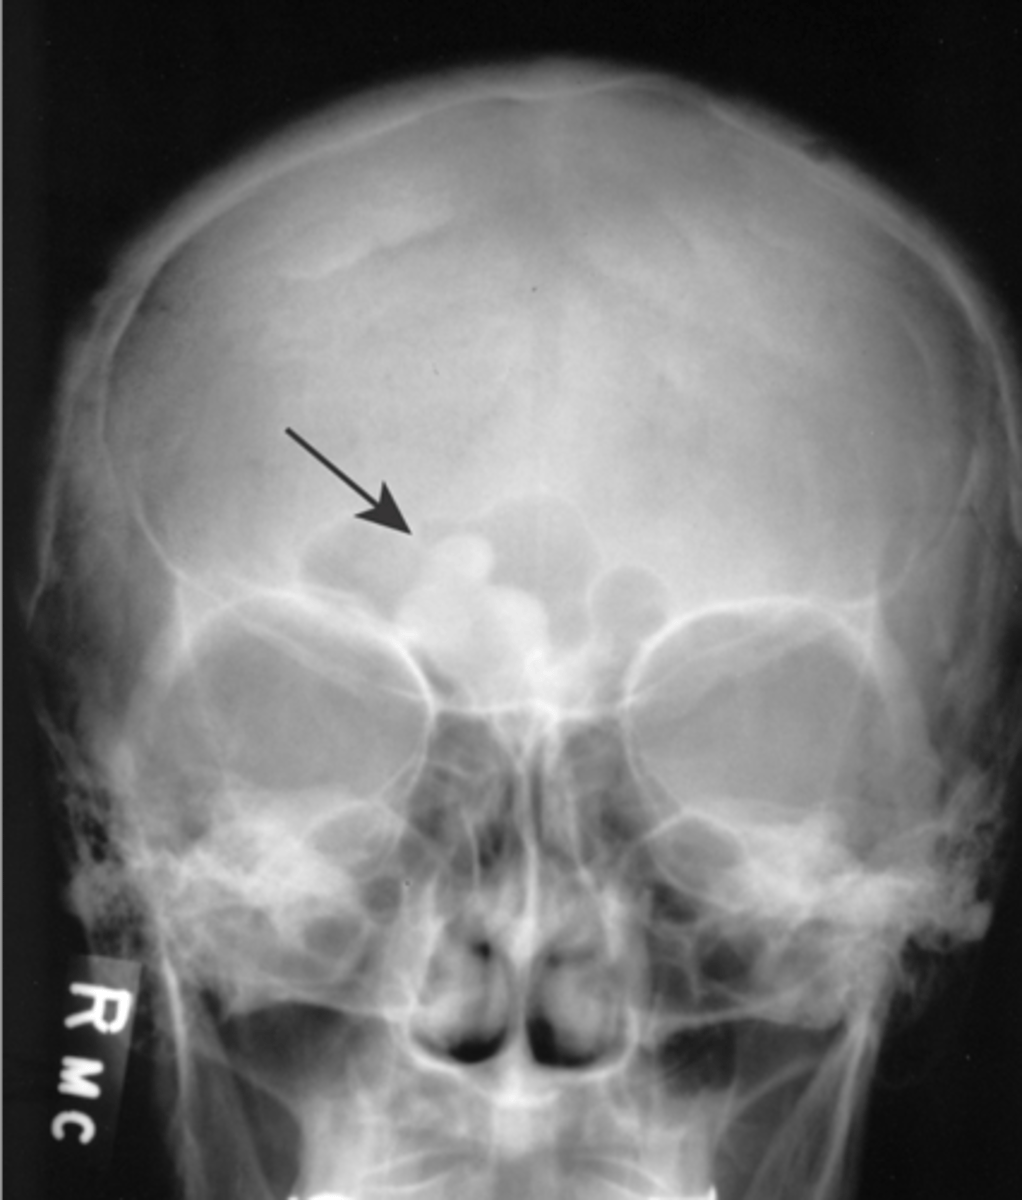

Beveled edge

ID radiographic feature of eosinophilic granuloma in the skull

<p>ID radiographic feature of eosinophilic granuloma in the skull</p>

74

New cards

Button sequestrum